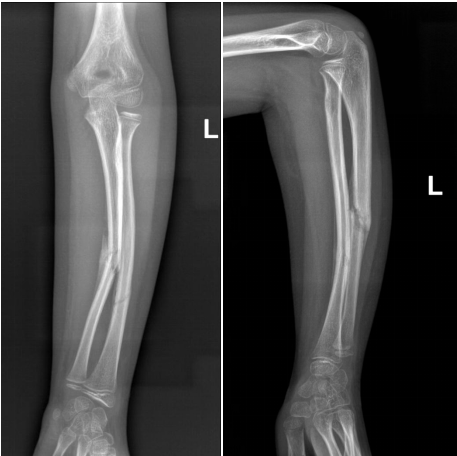

当地医院X片提示

“左侧尺桡骨干骨折”

术前骨折断端移位明显

经手法复位治疗无效

骨折端对位对线良好

术后骨折断端移位好转

力线纠正

手术切口小